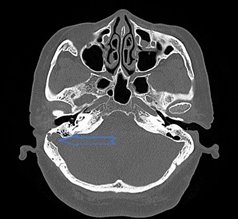

正常乙状窦 乙状窦前位+乙状窦憩室

乙状窦前位+乙状窦憩室+颈静脉球高位(黄色箭头)